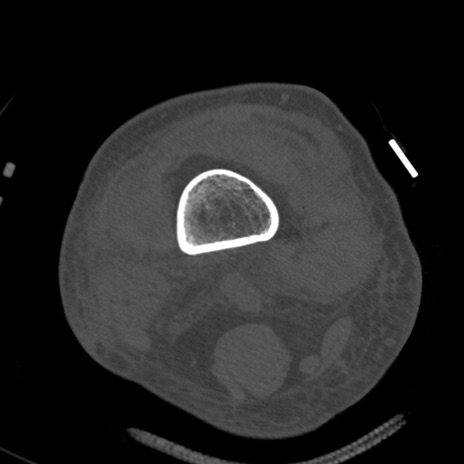

症例28 右膝関節CT(横断像)

右膝関節CT